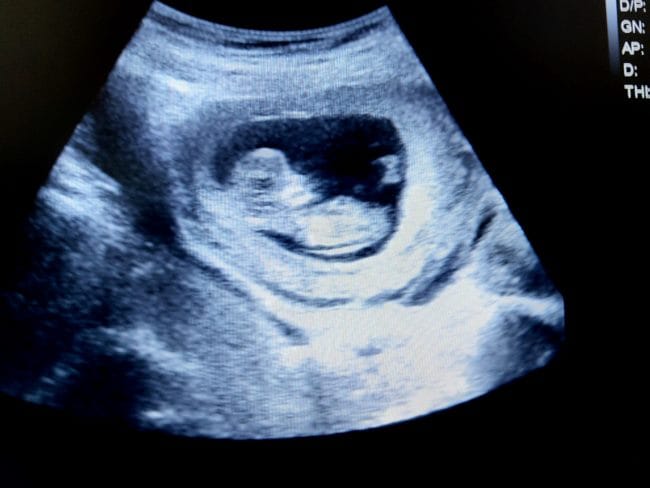

Detail di wajah ini memberi karakter unik pada janin dan menjadi salah satu pertanda perkembangan yang sehat. Meski masih sangat kecil, bentuk wajah bayi mulai bisa terlihat pada hasil USG. Proses ini menjadi awal dari identitas bayi yang terus berkembang sampai persalinan nanti.

Meskipun gerakan janin biasanya belum terdeteksi oleh ibu, aktivitas-aktivitas ini sudah dapat dilihat melalui pemeriksaan USG. Gerakan tersebut tidak hanya menandakan pertumbuhan yang normal, tetapi juga membantu janin beradaptasi dengan lingkungan di dalam rahim.